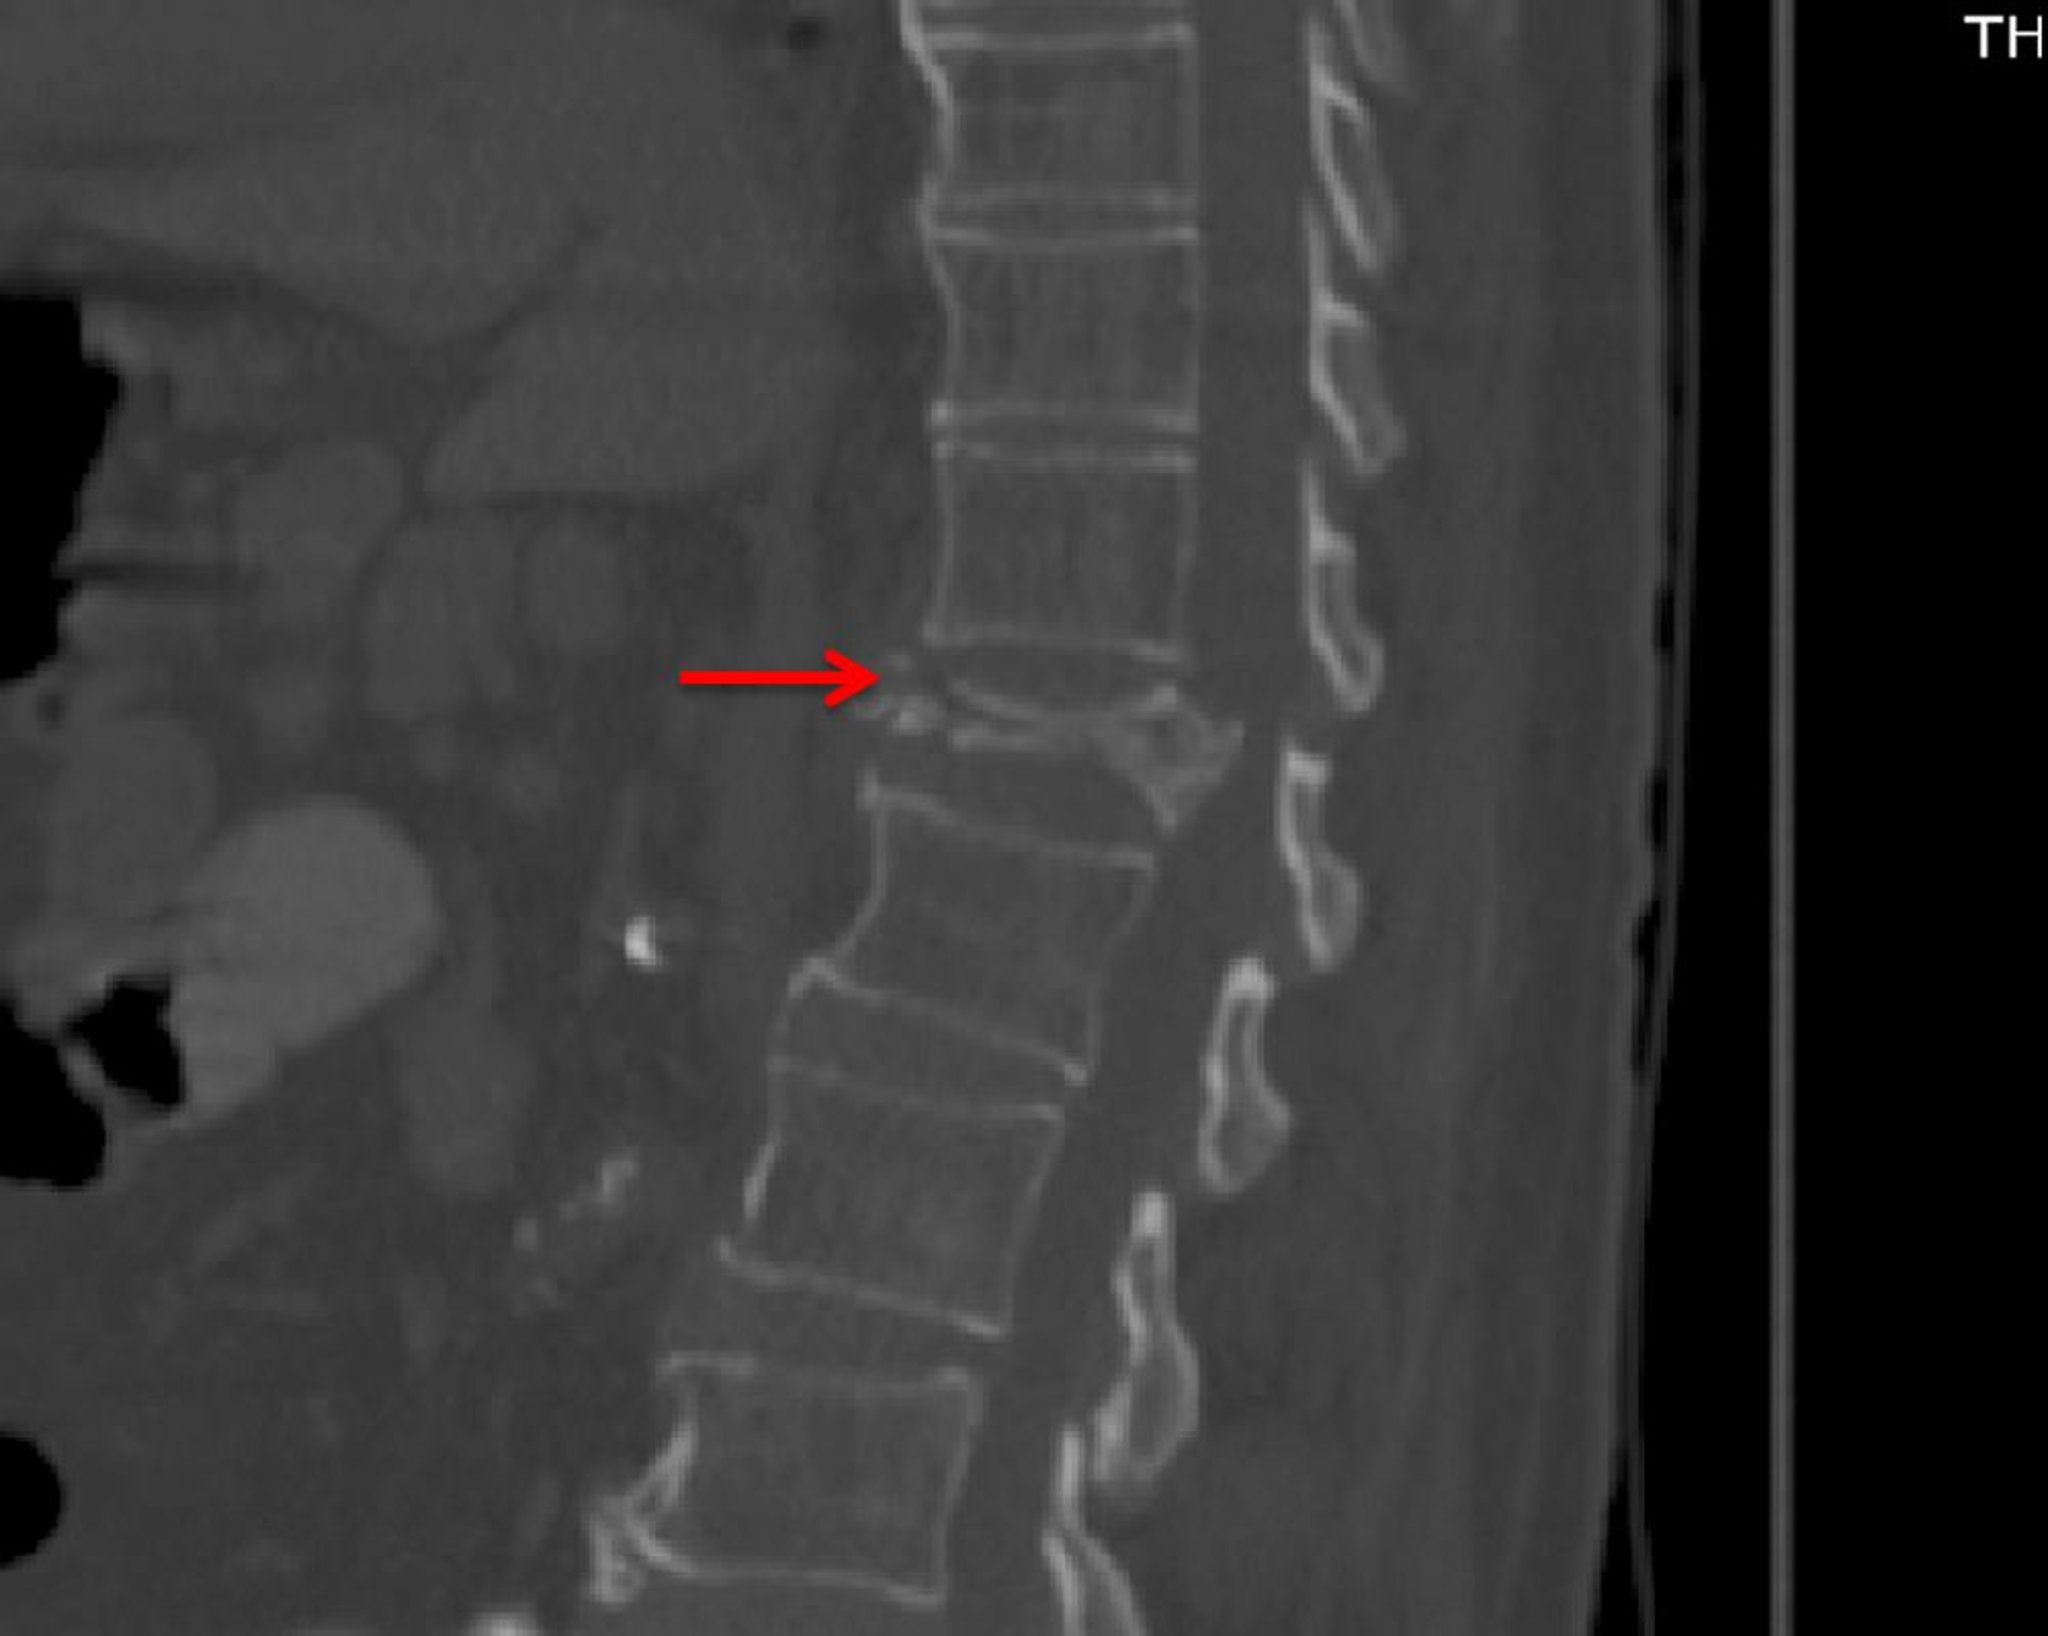

Fracture vertébrale par compression grave (TDM)

Cette TDM (vue sagittale) montre une fracture par compression marquée de T12 avec une maladie dégénérative légère (p. ex., ostéophytes du corps vertébral antérieur) ailleurs.